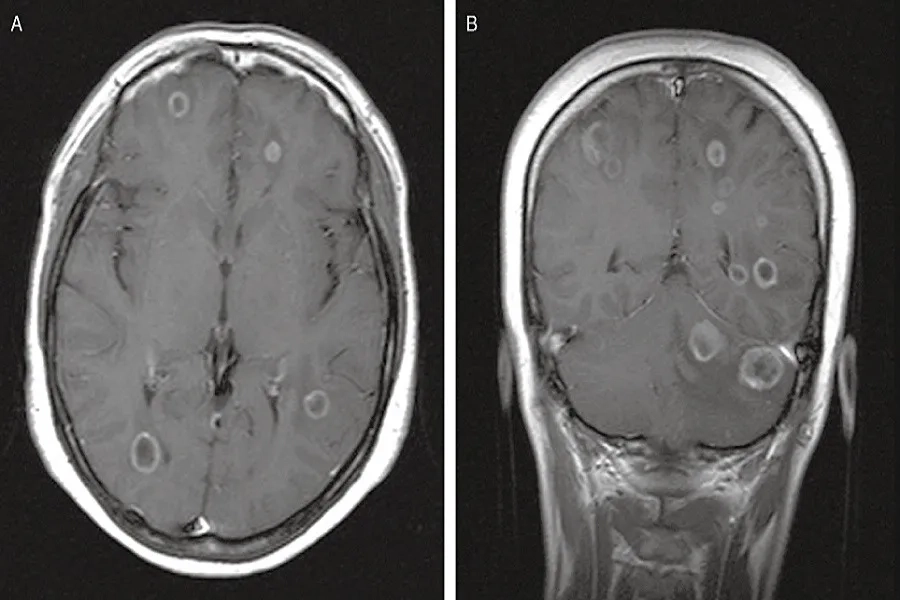

5. Ung thư cổ tử cung di căn não

Ung thư cổ tử cung di căn lên não là biến chứng nặng ở giai đoạn cuối, khi tế bào ung thư ảnh hưởng đến hệ thần kinh. Bạn có thể gặp đau đầu dữ dội, chóng mặt, buồn nôn, giảm thị lực, khó nói và yếu cơ, khiến việc đi lại trở nên khó khăn.

Bên cạnh đó, di căn não còn gây rối loạn tâm lý như dễ cáu gắt, thay đổi hành vi, giảm trí nhớ và lẫn lộn. Những biểu hiện này làm suy giảm nghiêm trọng chất lượng sống và cần được phát hiện, điều trị sớm để kiểm soát bệnh.